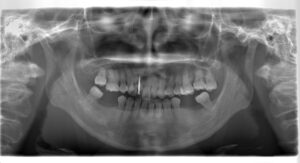

(治療前:写真左)

上顎の前歯は並ぶスペースが足りず、側切歯と犬歯が重なっています。

歯の真ん中がほぼ1本分ずれています。下顎は奥歯が欠損しており、歯槽骨が瘦せてしまっています。